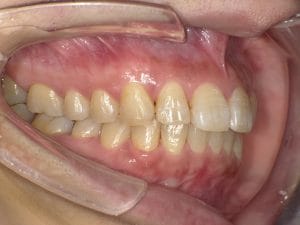

Case028 – セラミック矯正

歯並びと噛み合わせを治したいということを主訴に来院してくださった患者様の症例です。

前医の矯正専門医でマウスピースによる矯正では綺麗にならないといわれ、ワイヤー矯正はしたくなく、当院でセラミックで治したいということで来てくださいました。

初診時カウンセリングを含め計3回の診療、期間は三週間で前歯を内側に引っ込め、噛み合わせが交差咬合という不正咬合になってるところも治しました。

前歯が内側に引っ込むことで、口周りの軟組織もしまってお顔立ちもとても若々しくシュッとされ、より洗練されたイメージになりました。

当院はインビザラインによるマウスピース矯正、ワイヤー矯正、セラミック矯正の全ての矯正をやる事ができますが、その中で患者様のご希望、状態にあったもので、最善の治療をする事を心がけております。

担当 理事長 佐藤 悠野